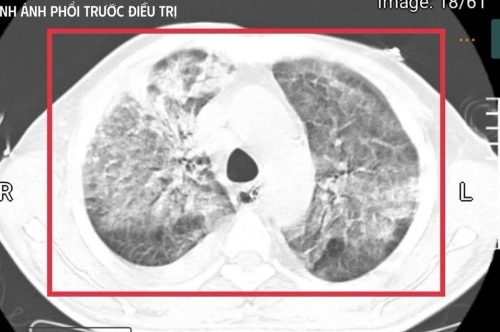

Tại đây, bệnh nhân được đặt nội khí quản thở máy; kết quả cấy máu xác định nhiễm Burkholderia pseudomallei - tác nhân gây bệnh Whitmore. Dù được điều trị ban đầu, tình trạng vẫn diễn tiến nặng nên gia đình xin chuyển về Việt Nam để tiếp tục điều trị.

Xét nghiệm cho thấy men gan và bilirubin tăng cao, rối loạn đông máu, creatinin tăng nhanh kèm vô niệu. Đây là biểu hiện của suy gan, suy thận cấp tiến triển. Nồng độ CK vượt quá 100.000 U/l, kèm đau cơ và nước tiểu sẫm màu, phù hợp với tiêu cơ vân cấp.

Các chỉ số viêm như CRP, PCT tăng rất cao, phản ánh tình trạng nhiễm trùng, nhiễm độc toàn thân dữ dội. Trên nền đó là đái tháo đường chưa kiểm soát và viêm gan C mạn, khiến cơ thể người bệnh càng suy sụp.

Theo bác sĩ Kim Anh, đây là một trong những thể tối cấp của whitmore, nhiễm khuẩn huyết nặng, suy đa tạng, rối loạn chuyển hoá sâu và nguy cơ tử vong rất lớn trong thời gian rất ngắn nếu không được hồi sức tích cực ngay lập tức.